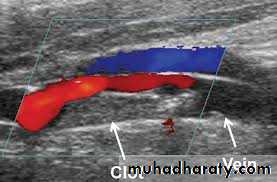

Compression ultrasound or doppler us is the imaging modality of choice .

Doppler us in DVT